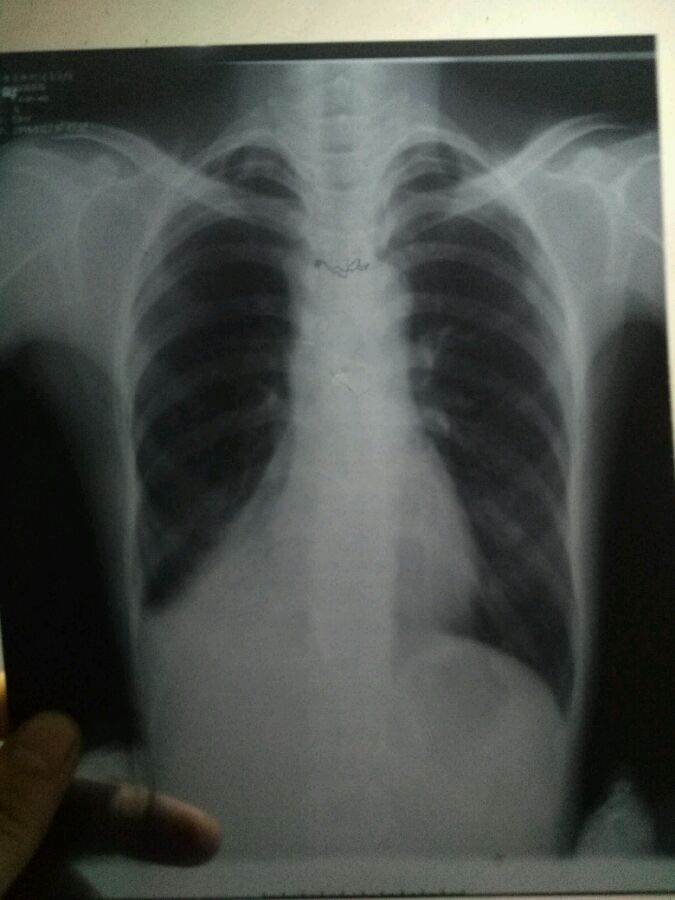

我妈妈最近老是咳嗽,去做了个ct,医生说不排除结核,有人会看吗?看了好几个医院说法都不一样。

结核的临床症状,低热盗汗,咯血,以及食欲不振,,与你症状符合吗?